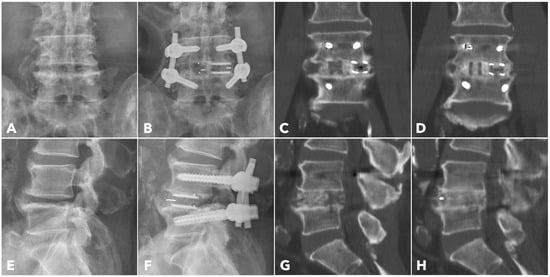

Figure 6. A 67-year-old male patient underwent BETLIF at L4-5 due to recurrent lumbar disc herniation and painful disc degeneration (A,E). The postoperative X-rays showed restoration of the disc height with double cages in the disc space (B,F). The immediate postoperative CT scan demonstrated the cage positions and no violation of the bony endplates (C,G). The 1-year CT scan revealed Bridwell grade I solid fusion with remodeling of the bone graft (D,H).